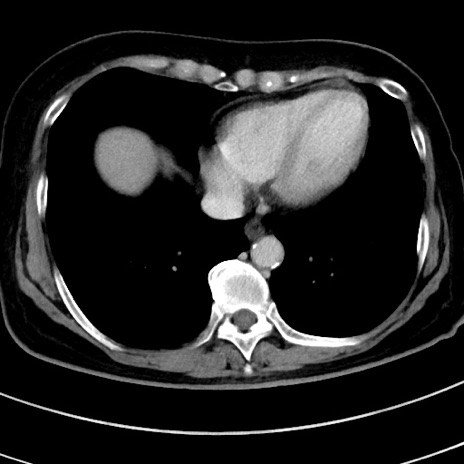

症例9(横断像)

【症例】 60歳代女性

【主訴】むかつき、みぞおちの痛み

【現病歴】3日前よりむかつきがあり、食事がとれない。

【既往歴】糖尿病

【身体所見】発熱なし、心窩部圧痛軽度あるも、腹膜刺激症状なし。

【データ】WBC 7400、CRP 1.92